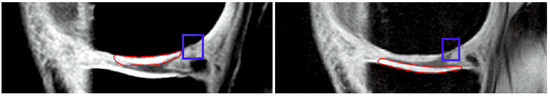

Novel Hybrid Optimized Clustering Schemes with Genetic Algorithm and PSO for Segmentation and Classification of Articular Cartilage Loss from MR Images

by Jan Kubicek, Alice Varysova, Martin Cerny, Jiri Skandera, David Oczka, Martin Augustynek and Marek Penhaker

Mathematics 2023, 11(4), 1027; https://doi.org/10.3390/math11041027 - 17 Feb 2023

Medical image segmentation plays an indispensable role in the identification of articular cartilage, tibial and femoral bones from magnetic resonance imaging (MRI). There are various image segmentation strategies that can be used to identify the knee structures of interest. Among the most popular [...] Read more.

Medical image segmentation plays an indispensable role in the identification of articular cartilage, tibial and femoral bones from magnetic resonance imaging (MRI). There are various image segmentation strategies that can be used to identify the knee structures of interest. Among the most popular are the methods based on non-hierarchical clustering, including the algorithms K-means and fuzzy C-means (FCM). Although these algorithms have been used in many studies for regional image segmentation, they have two essential drawbacks that limit their performance and accuracy of segmentation. Firstly, they rely on a precise selection of initial centroids, which is usually conducted randomly, and secondly, these algorithms are sensitive enough to image noise and artifacts, which may deteriorate the segmentation performance. Based on such limitations, we propose, in this study, two novel alternative metaheuristic hybrid schemes: non-hierarchical clustering, driven by a genetic algorithm, and Particle Swarm Optimization (PSO) with fitness function, which utilizes Kapur’s entropy and statistical variance. The goal of these optimization elements is to find the optimal distribution of centroids for the knee MR image segmentation model. As a part of this study, we provide comprehensive testing of the robustness of these novel segmentation algorithms upon the image noise generators. This includes Gaussian, Speckle, and impulsive Salt and Pepper noise with dynamic noise to objectively report the robustness of the proposed segmentation strategies in contrast with conventional K-means and FCM. This study reveals practical applications of the proposed algorithms for articular cartilage extraction and the consequent classification performance of early osteoarthritis based on segmentation models and convolutional neural networks (CNN). Here, we provide a comparative analysis of GoogLeNet and ResNet 18 with various hyperparameter settings, where we achieved 99.92% accuracy for the best classification configuration for early cartilage loss recognition. Full article

Show Figures

Figure 1